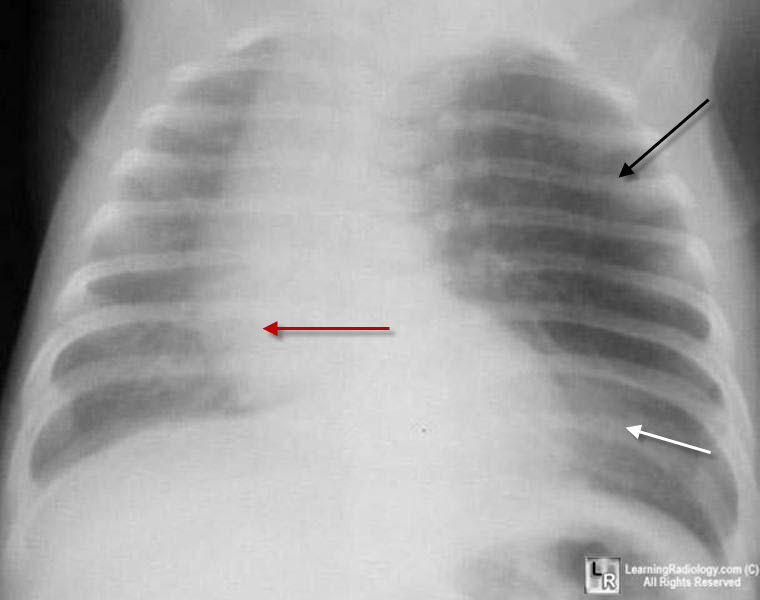

Lobar consolidation involving the right middle lobe, right lower lobe | Download Scientific

Lobar consolidation involving the right middle lobe, right lower lobe | Download Scientific  ENFISEMA LOBAR CONGENITO PDF

Lobar pneumonic consolidation in the right inferior lobe | Download Scientific Diagram  ENFISEMA LOBAR CONGENITO PDF

Lobar consolidation | Radiology Reference Article | Radiopaedia.org  PPT - Atelectasis PowerPoint Presentation - ID:6185976

Chest radiograph reveals multi-lobar consolidation in bilateral lower | Download Scientific  Bilateral multifocal acute lobar nephronia caused by Enterococcus faecalis | BMJ Case Reports